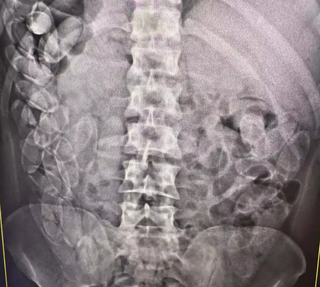

O médico Manoel João da Costa Oliveira, cirurgião da Santa Casa de Corumbá (MS), já operou dois casos de pessoas que transportavam cocaína dentro do corpo, o primeiro deles há 15 anos, tornando-se um dos pioneiros no Brasil nesse tipo de procedimento para salvar vidas. Nesta semana, ele atendeu uma boliviana de 34 anos que chegou em estado grave, com 78 cápsulas de droga no intestino, mais de dois quilos de cocaína.

Manoel João da Costa Oliveira — Essa foi a segunda paciente deste ano. São pessoas que fazem uma besteira dessas por desespero. Pobres, coitadas mesmo. Essa mulher chegou ao pronto-socorro com dor abdominal intensa. As cápsulas são grandes e volumosas — ela tinha 78 no corpo. Estava há quase cinco dias com isso no intestino. Quando abrimos, encontramos mais de dois quilos de cocaína pura. Ela corria risco real de morte.

O sistema digestivo é muito extenso. O intestino delgado tem cerca de oito metros de comprimento; o grosso, mais dois. No estômago dela havia quatro cápsulas. Mas o perigo é enorme: se uma só se rompe, a pessoa morre em minutos por overdose. É uma morte instantânea.